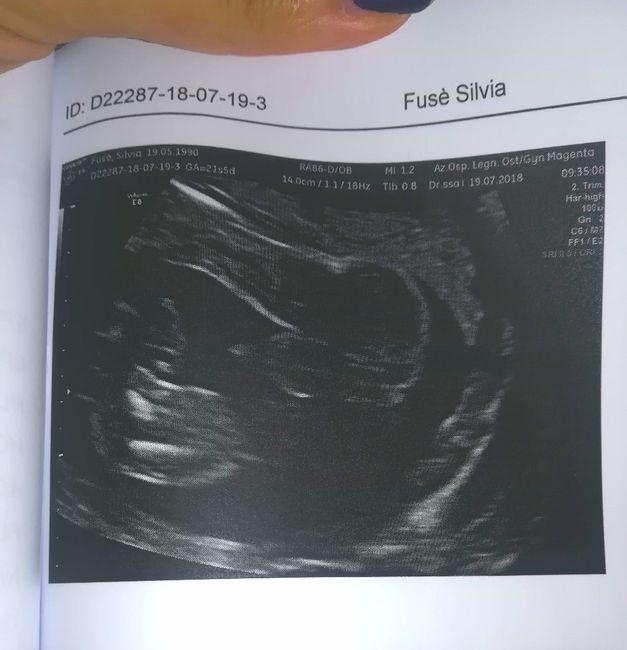

Questa é del mio pastrugno alla morfologica.

Anche noi non sapevamo il sesso fino alla morfologica ma poi... Smiley xd direi che più chiaro di così 😁

Ecografia con sesso evidente 1